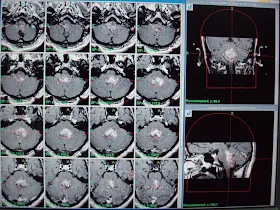

This, 26 years nice man from Karachi had undergone insertion of VP shunt on right side on November 22, 2010 on radio diagnosis of heterogeneous enhancing solid cum cystic mass in posterior fossa in fourth ventricle causing hydrocephalus. This was diagnosed when patient had presented with severe headache on and off associated with vomiting worst since last month and blurred vision since one month.

On referral, he had presented some improvement in headache and vomiting and significant improvement in blurring of vision. Clinical examination had revealed no obvious neurologic deficit. MRI brain spectroscopy had revealed markedly elevated Choline levels up to 399. Patient has referred us for the management with GKSRS. Risk of GKSRS explained all in Urdu along with requirement of strict follow up. These agreed upon wished to proceed. He had treatment with following prescription,

Target | Location | Prescription | Volume |

A | Ependymoma. | 12Gy @ 50% | 18.6 cm³ |

Multiple isocenters with 18, 14 & 8 mm collimator used in APS mode. He had discharged on tapering doses of Dexamethasone and advised follow up after 3 months